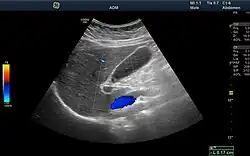

Medical ultrasound uses high frequency broadband sound waves in the megahertz range that are reflected by tissue to varying degrees to produce (up to 3D) images. This is commonly associated with imaging the fetus in pregnant women. Uses of ultrasound are much broader, however. Other important uses include imaging the abdominal organs, heart, breast, muscles, tendons, arteries and veins. While it may provide less anatomical detail than techniques such as CT or MRI, it has several advantages which make it ideal in numerous situations, in particular that it studies the function of moving structures in real-time, emits no ionizing radiation, and contains speckle that can be used in elastography. Ultrasound is also used as a popular research tool for capturing raw data, that can be made available through an ultrasound research interface, for the purpose of tissue characterization and implementation of new image processing techniques. The concepts of ultrasound differ from other medical imaging modalities in the fact that it is operated by the transmission and receipt of sound waves. The high frequency sound waves are sent into the tissue and depending on the composition of the different tissues; the signal will be attenuated and returned at separate intervals. A path of reflected sound waves in a multilayered structure can be defined by an input acoustic impedance (ultrasound sound wave) and the Reflection and transmission coefficients of the relative structures.[20] It is very safe to use and does not appear to cause any adverse effects. It is also relatively inexpensive and quick to perform. Ultrasound scanners can be taken to critically ill patients in intensive care units, avoiding the danger caused while moving the patient to the radiology department. The real-time moving image obtained can be used to guide drainage and biopsy procedures. Doppler capabilities on modern scanners allow the blood flow in arteries and veins to be assessed.

Volume rendering techniques have been developed to enable CT, MRI and ultrasound scanning software to produce 3D images for the physician.[43] Traditionally CT and MRI scans produced 2D static output on film. To produce 3D images, many scans are made and then combined by computers to produce a 3D model, which can then be manipulated by the physician. 3D ultrasounds are produced using a somewhat similar technique. In diagnosing disease of the viscera of the abdomen, ultrasound is particularly sensitive on imaging of biliary tract, urinary tract and female reproductive organs (ovary, fallopian tubes). As for example, diagnosis of gallstone by dilatation of common bile duct and stone in the common bile duct. With the ability to visualize important structures in great detail, 3D visualization methods are a valuable resource for the diagnosis and surgical treatment of many pathologies. It was a key resource for the famous, but ultimately unsuccessful attempt by Singaporean surgeons to separate Iranian twins Ladan and Laleh Bijani in 2003. The 3D equipment was used previously for similar operations with great success.